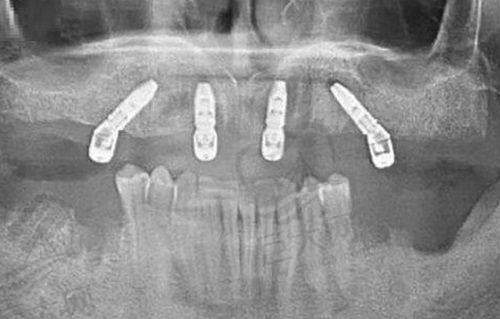

牙博仕口腔拥有专门的正畸中 心,采用了精良的数字化牙齿矫正技术。这一技术的优势显著,在矫正手术前,患者就能通过相关设备看到矫正牙齿后的成效。借助计算机设备,医生可以对每一颗牙齿需要移动的位置、方向、角度都进行详细的参数设定,整个整牙过程都是严格按照这些严谨的参数进行的。

这种数字化的矫正方式大大提高了矫正的正确性和成效。与传统的矫正方法相比,它能更好地预测矫正结果,减少矫正过程中的不确定性,从而提高患者的术后满意度。许多在牙博仕口腔接受牙齿矫正的患者都表示,看到术前模拟的矫正成效后,心里更有底了,而且实际矫正成效也与预期相符,甚至超出了预期。